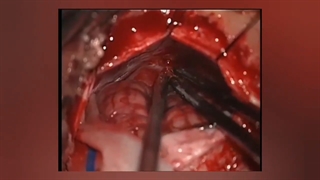

مننژیوم پتروکلایوال